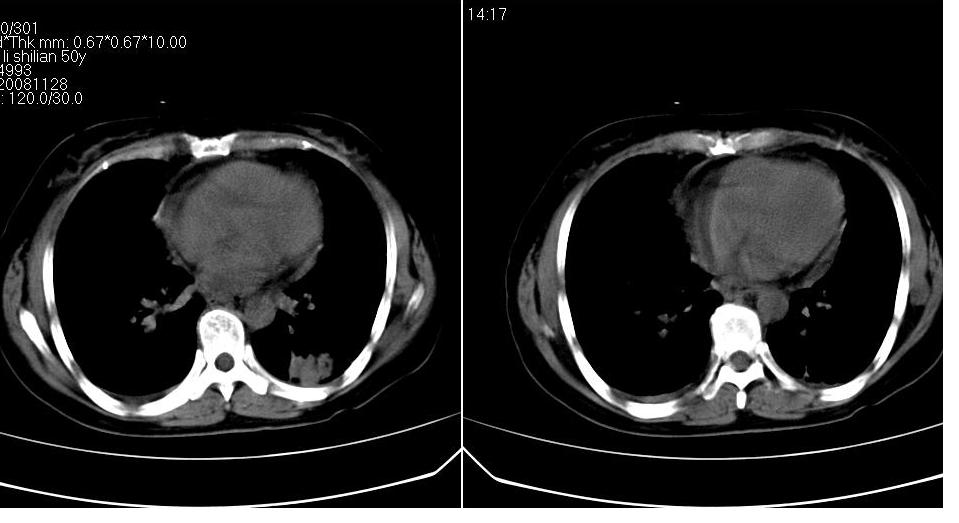

标题: CT16839:胸部CT平扫

女 50岁,在其他医院确诊肺癌.

支持 右肺上叶肺癌并两肺及纵隔转移。

考虑 肺癌伴肺及纵隔转移,心包膜增厚